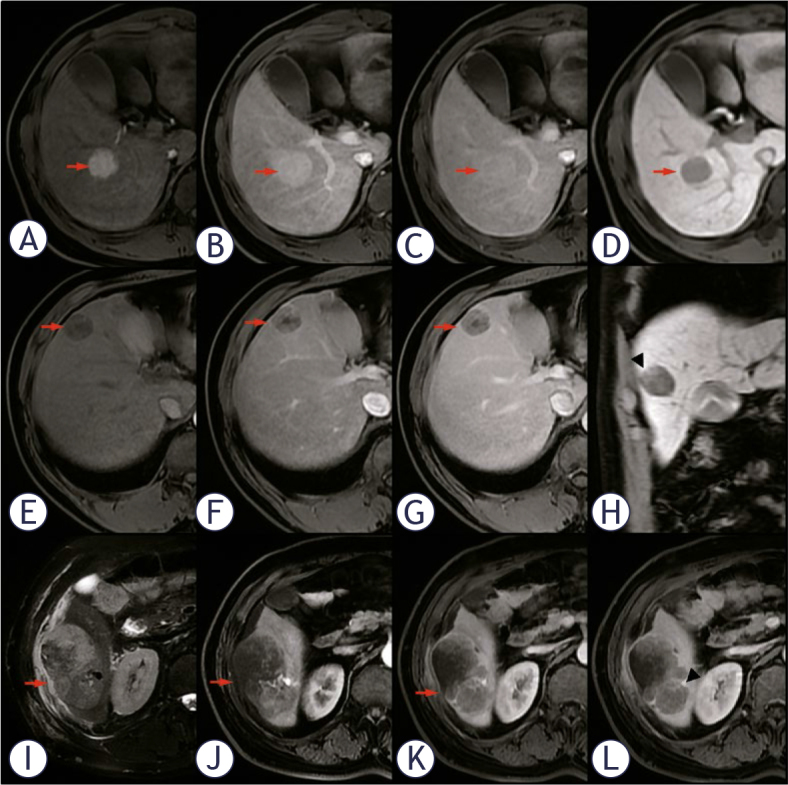

Results: Four factors associated with MVI (P < 0.05) were related, including non-solitary growth types, no/mini enhanced mode, peritumoral enhancement on arterial phase, and peritumoral hypointensity on hepatobiliary phase. Only the ratio of the maximum and minimum tumor diameter (Max/Min-R), confluent multinodule growth type, and non-washin/washout enhanced modes of those MVI-positive patients showed a strong correlation with M2 grade. The areas under the receiver operating characteristic (ROC) curves were 0.885 (95% confidence intervals [CI]: 0.833-0.937) in identifying MVI and 0.805 (95% CI: 0.703-0.908) in predicting its M2 grade, respectively. The nomograms demonstrated a high goodness-of-fit and clinical benefits in DCA and calibration curve.

Conclusions: Enhancement modes and tumor growth patterns of preoperative MRI were independent risk factors of MVI severity, which were valuable for facilitating individualized decision-making.